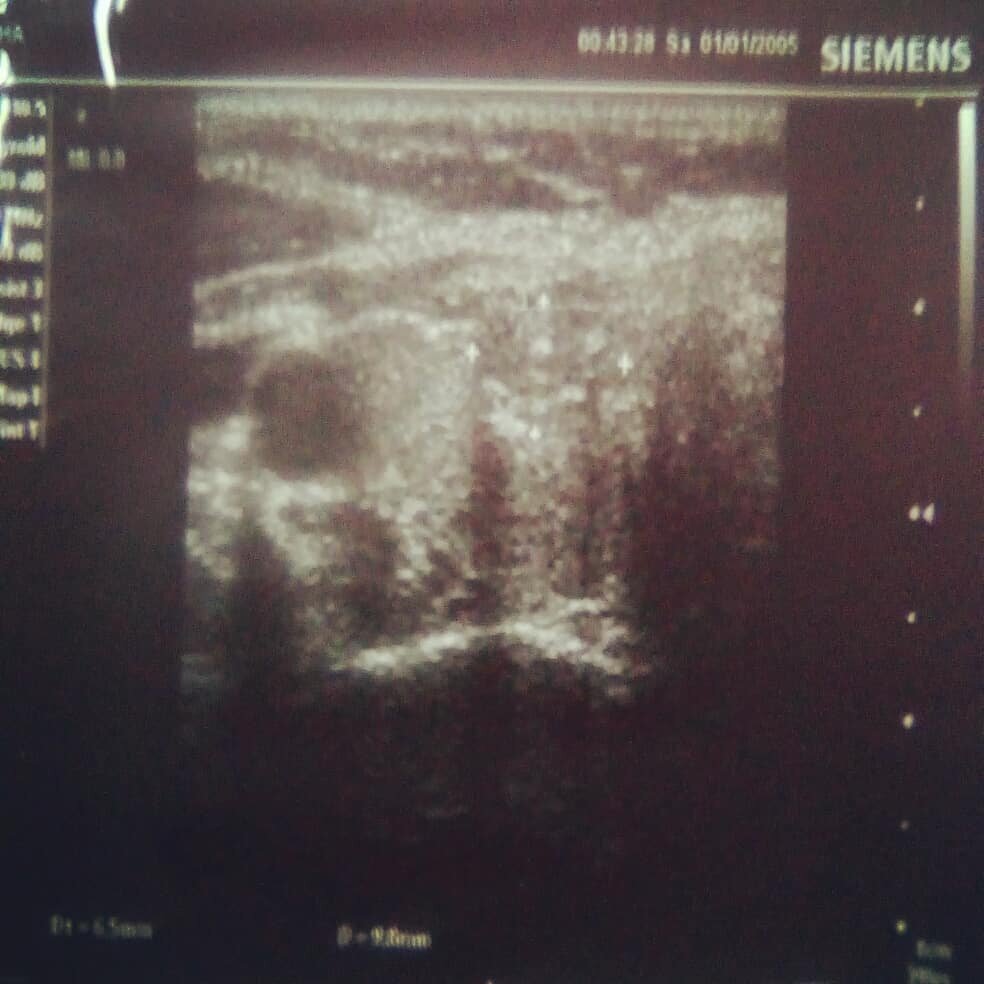

На фото узел, проявляющий явные признаки злокачественности.

1. Гипоэхогенность (простым языком - более темный узел на светлом фоне ткани щитовидной железы)

2. Неровные, нечеткие контуры

3. Преобладание высоты узла над шириной

4. Микрокальцинаты (светлые включения в узле)